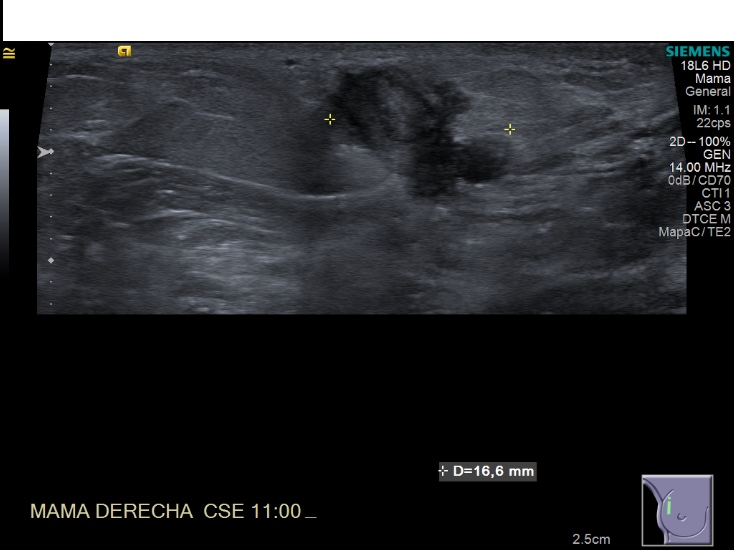

Crioablacion de tumor en mama derecha